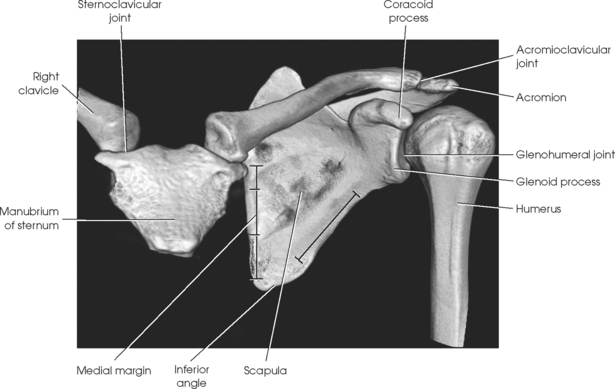

The shoulder girdle is formed by two bones—the clavicle and scapula. The function of these bones is to connect the upper limb to the trunk. Although the alignment of these two bones is considered a girdle, it is incomplete in front and in back. The girdle is completed in front by the sternum, which articulates with the medial end of the clavicle. The scapulae are widely separated in the back. The proximal portion of the humerus is part of the upper limb and not the shoulder girdle proper; however, because the proximal humerus is included in the shoulder joint, its anatomy is considered with that of the shoulder girdle (Figs. 5-1 and 5-2).

The clavicle, classified as a long bone, has a body and two articular extremities (see Fig. 5-1). The clavicle lies in a horizontal oblique plane just above the first rib and forms the anterior part of the shoulder girdle. The lateral aspect is termed the acromial extremity, and it articulates with the acromion process of the scapula. The medial aspect, termed the sternal extremity, articulates with the manubrium of the sternum and the first costal cartilage. The clavicle, which serves as a fulcrum for the movements of the arm, is doubly curved for strength. The curvature is more acute in males than in females.

The scapula, classified as a flat bone, forms the posterior part of the shoulder girdle (Figs. 5-3 and 5-4). Triangular in shape, the scapula has two surfaces, three borders, and three angles. Lying on the superoposterior thorax between the second and seventh ribs, the medial border of the scapula runs parallel with the vertebral column. The body of the bone is arched from top to bottom for greater strength, and its surfaces serve as the attachment sites of numerous muscles. The flat aspect of the bone lies at about a 45- to 60-degree angle in relation to the anatomic position (see Fig. 5-2).